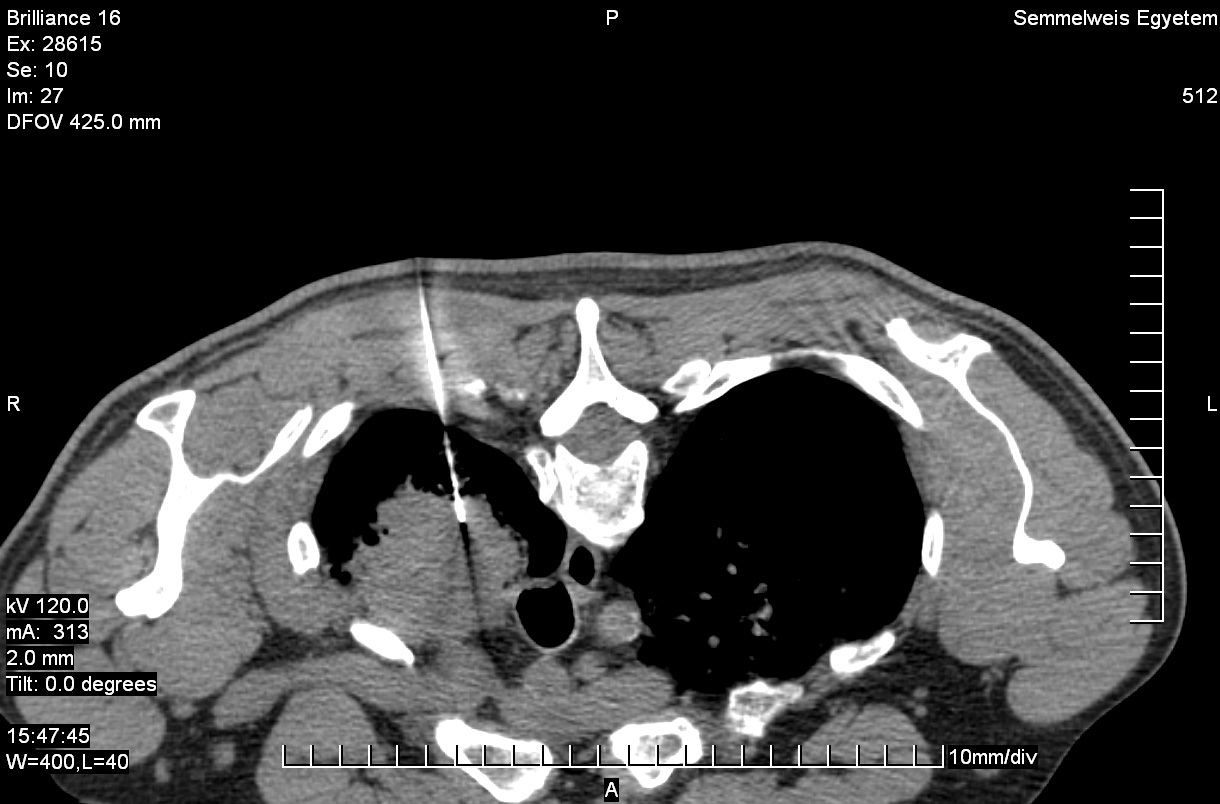

19.2.2.2. CT guided biopsy

Ideal method if the lesion is located either in the chest (figure 5.), mediastinum, retroperitoneum (figure 6.) or the pelvis.

Image

Figure 5. – CT guided thoracic biopsy

Advantages:

1. Excellent spatial resolution.

2. Bone and intestinal gas do not hinder sampling.

3. Less operator dependent than US guided biopsy.

Disadvantages:

1. Uses ionizing radiation.

2. No real time control.

3. Less available, relatively more expensive.

4. Can only be performed in the CT lab.

5. More time consuming.